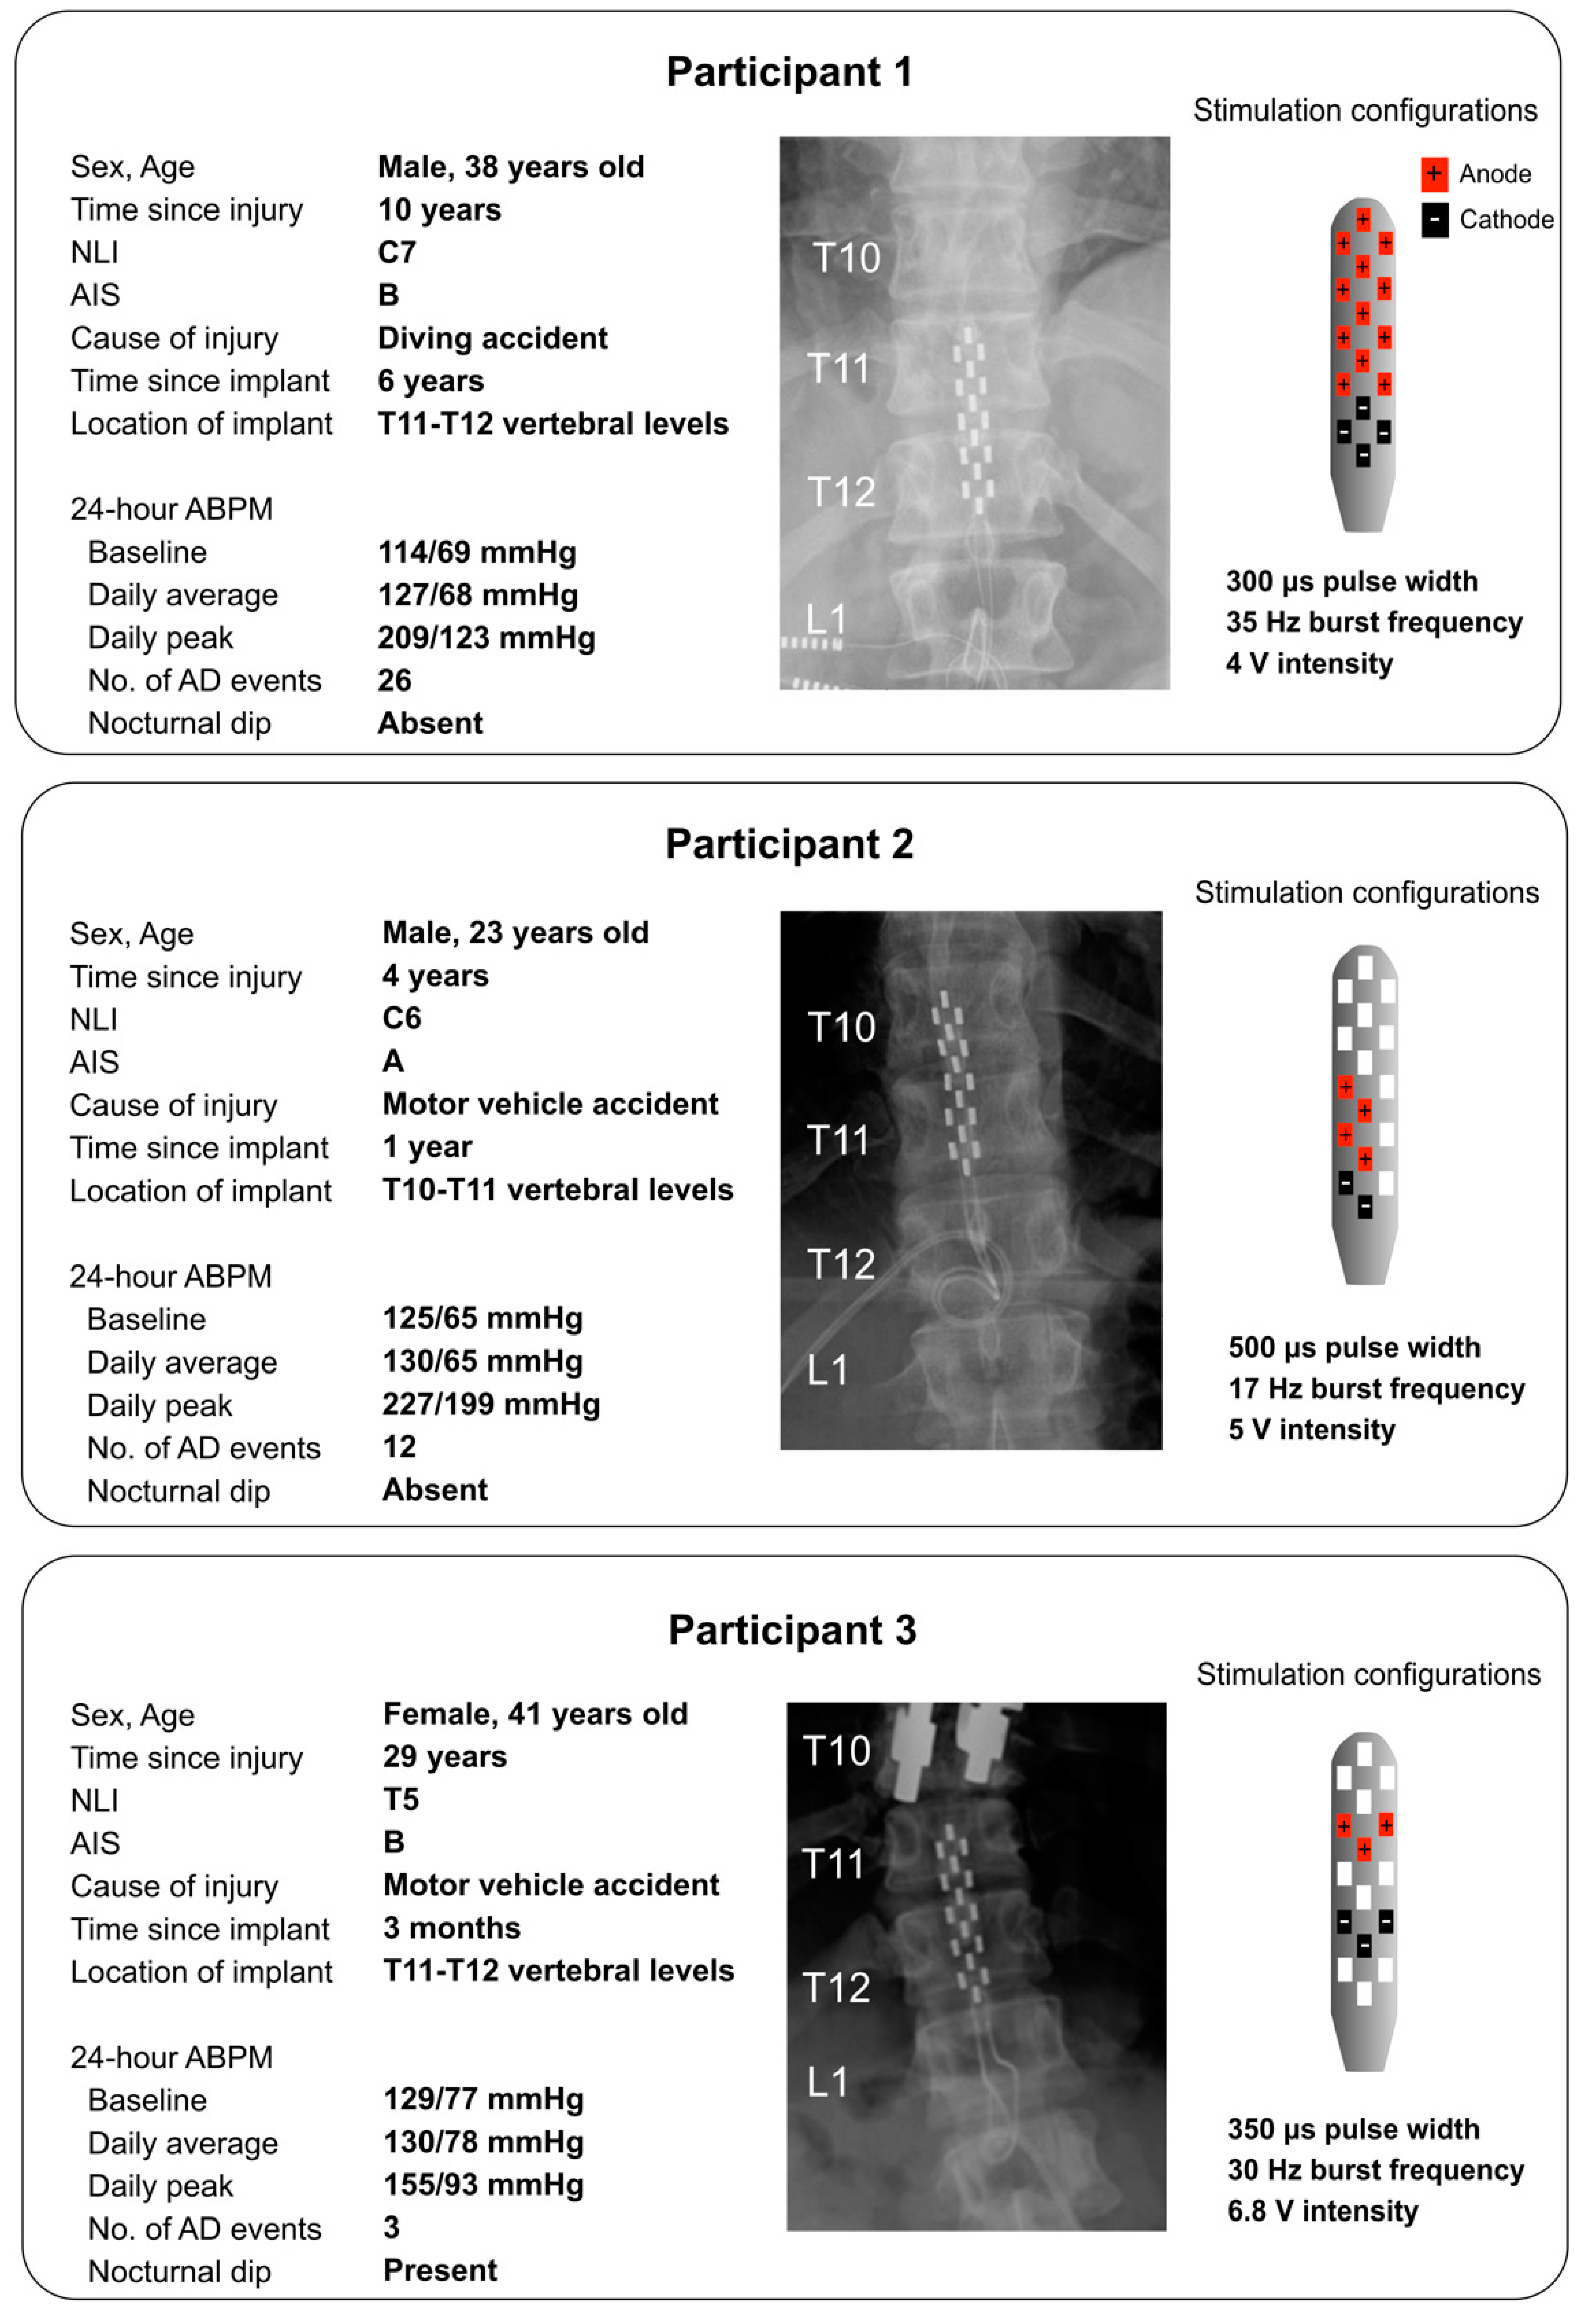

| Participant 1 | Participant 2 | Participant 3 | ||||

|---|---|---|---|---|---|---|

| Without eSCS | With eSCS | Without eSCS | With eSCS | Without eSCS | With eSCS | |

| Baseline SBP (mmHg) | 110 ± 10 | 118 ± 12 | 102 ± 2 | 96 ± 1 | 134 ± 1 | 137 ± 4 |

| Baseline DBP (mmHg) | 63 ± 7 | 66 ± 10 | 62 ± 3 | 53 ± 2 | 93 ± 5 | 91 ± 1 |

| Baseline HR (bpm) | 71 ± 8 | 71 ± 14 | 47 ± 1 | 46 ± 1 | 69 ± 0.1 | 70 ± 1 |

| Baseline LF wavelet power (a.u.) | 0.0047 ± 0.0030 | 0.0051 ± 0.0015 | 0.0050 ± 0.0044 | 0.0050 ± 0.0013 | 0.0058 ± 0.0014 | 0.0052 ± 0.0003 |

| ∆ SBP during DARS (mmHg) | 31 ± 14 | 16 ± 0.2 | 22 ± 1 | 13 ± 3 | 26 ± 2 | 8 ± 5 |

| ∆ DBP during DARS (mmHg) | 13 ± 6 | 4 ± 2 | 14 ± 2 | 7 ± 1 | 7 ± 0.2 | −1 ± 2 |

| ∆ HR during DARS (bpm) | −20 ± 8 | −9 ± 3 | −5 ± 1 | −3 ± 0.2 | −8 ± 2 | −2 ± 2 |

| ∆ LF wavelet power during DARS (a.u.) | 0.0021 ± 0.0006 | −0.0001 ± 0.0011 | 0.0015 ± 0.0003 | −0.0002 ± 0.0002 | 0.0029 ± 0.0001 | 0.0007 ± 0.0003 |